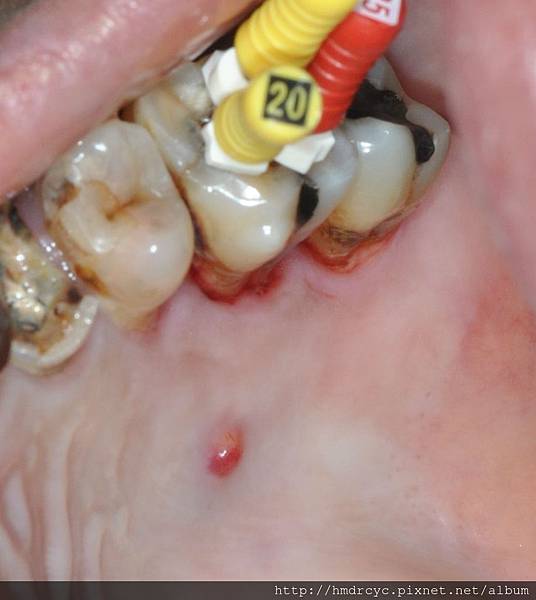

另外一個根管治療完還會痛的原因是牙根感染化膿

蛀牙引起牙神經壞死

膿順著牙根管開始感染下面的骨頭

破壞骨頭後形成一個膿包

在口腔裡面的狀況就是這樣

嚴格的說膿包其實在骨頭裡面

在口腔裡面看到的是膿流出來的開口